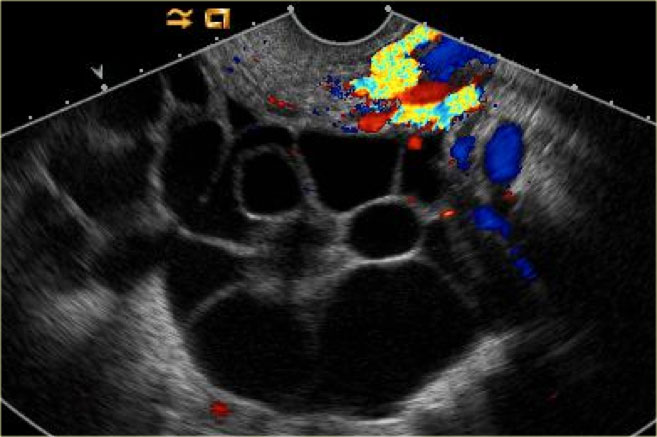

On imaging there is - usually bilateral - ovarian enlargement with multiloculated cyst that can totally replace the ovary.

Theca lutein cysts: US images of a young pregnant woman. In both ovaries there are multiple cysts. Right image shows an invasive uterine mass, consistent with invasive molar pregnancy. Theca lutein cysts: US images of a young pregnant woman. In both ovaries there are multiple cysts. Right image shows an invasive uterine mass, consistent with invasive molar pregnancy.

The US images are of a young pregnant woman, who had multiple ovarian cysts. The other ovary is not shown but showed a similar appearance.

The features needed to make the diagnosis of ovarian hyperstimulation syndrome are in the clinical history - a young pregnant woman - and in the last image of the uterus, which shows an invasive uterine mass, consistent with invasive molar pregnancy.